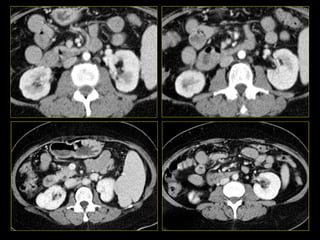

Caso # 5 ♀ ,  5ta década de la vida Antecedente de cirrosis hepática, hepatitis C y  Diabetes Mellitus. Ingresa con dolor abdominal por lo que se realiza estudio de TC en cortes axiales y coronales, fases arterial y venosa.

FASE ARTERIAL FASE VENOSA

Hallazgos Caso # 5 Área hipodensa en tercio medio del riñón izquierdo, sugestiva de lesión neoplásica a descartar área de inflamación focal.

SE INICIA ANTIBIOTICOTERAPIA Y SE INDICA ESTUDIO DE CONTROL A LOS 5  MESES.

Hallazgos estudio de control Caso # 5: La lesión ha desaparecido, lo que fue indicativo de que  se trataba de proceso inflamatorio focal resuelto posterior a manejo medico.